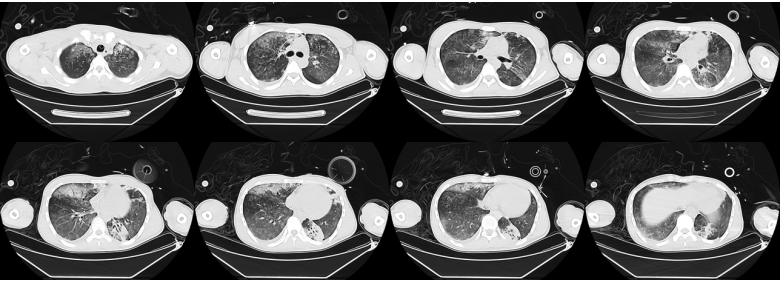

复查胸部CT(入院前3天/入院前2天):双肺炎症性病变,下肺实变呈加重趋势,右下肺有新发实变影(图2,图3)。患者影像学从单叶进展为多叶多段病变,渗出影进展非常快。左下肺影像学表现与大叶性肺炎不同,大叶性肺炎通常伴有支气管充气征,但该患者影像学完全无支气管充气征。对比患者三次影像学表现可见病变进展异常迅速。纵隔窗也提示患者病变迅速进展,且实变中未见支气管气相。

图2 患者外院胸部CT(入院前3天)

图3 患者外院胸部CT(入院前2天)